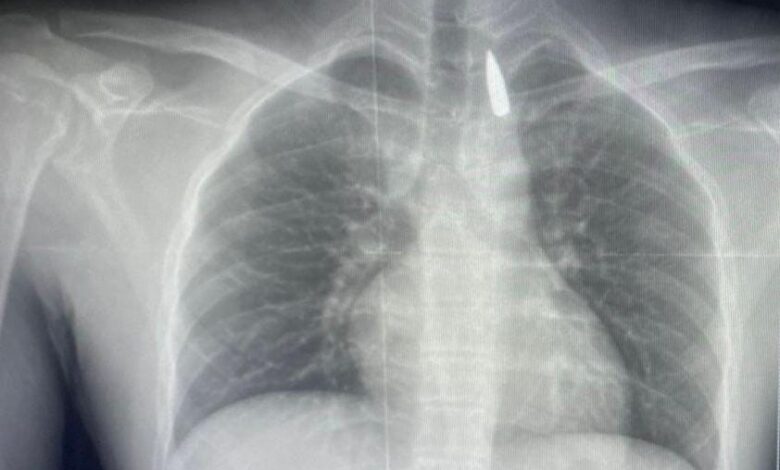

وأوضح الدكتور تامر عبد الله، عميد كلية الطب ورئيس مجلس إدارة المستشفيات الجامعية، أنه في يوم 21 أكتوبر 2025 تمكن فريق من أطباء قسم جراحة القلب والصدر والتخدير والمعاونين من إجراء جراحة دقيقة بالغة الخطورة لأحد المرضى المحجوزين من قطاع غزة،

والذي كان قد تعرض لإصابة بطلق ناري في الرأس منذ فترة، استقر المقذوف على إثرها داخل تجويف القفص الصدري قرب الشريان الأورطي، وهو أكبر وأهم شرايين الجسم والمسؤول عن تغذية جميع الأعضاء الحيوية، وأضاف أن الفريق الطبي، رغم دقة الحالة وتعقيدها، نجح في استخراج المقذوف بأمان بعد عملية جراحية نادرة استمرت عدة ساعات داخل المستشفى الجامعي الجديد،

حيث خضع المريض بعدها للرعاية الطبية اللازمة، وحالته حاليًا مستقرة وتحت المتابعة الدقيقة من الفريق المختص.